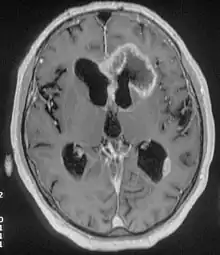

Tumor cerebral

Um tumor cerebral ocorre quando se formam células anormais no cérebro.[2] Existem dois tipos principais de tumores: tumores malignos e tumores benignos.[2] Os tumores cancerosos podem ser divididos em tumores primários, que se começam a formar no próprio cérebro, ou tumores secundários, que se espalharam a partir de outras partes do corpo, denominados metástases cerebrais.[1] Este artigo descreve principalmente os tumores que têm origem no cérebro. Todos os tipos de tumores cerebrais manifestam sintomas que variam conforme a parte do cérebro afetada.[2] Os sintomas incluem dores de cabeça, convulsões, problemas de visão, vómitos e perturbações mentais.[1][7] A dor de cabeça é geralmente mais intensa durante a manhã e desaparece após os vómitos.[2] Alguns tipos de tumor podem provocar dificuldade em caminhar, falar ou a nível de sensibilidade.[3]

| Método de diagnóstico | Tomografia computorizada, ressonância magnética, biópsia[1][2] |

A causa da maior parte dos tumores cerebrais é desconhecida.[2] Entre os fatores de risco que podem ocasionalmente estar envolvidos estão uma série de condições hereditárias conhecidas como neurofibromatoses, assim como a exposição ao cloreto de vinil, ao vírus Epstein-Barr e à radiação ionizante.[2][1][3] Embora tenham sido levantadas preocupações quanto ao uso de telemóveis, as evidências não são claras.[3] Os tipos mais comuns de tumores primários em adultos são os meningiomas (geralmente benignos) e os astrocitomas, tais como os gliobastomas.[1] Em crianças, o tipo mais comum são os meduloblastomas malignos.[3] O diagnóstico é geralmente realizado através de exame clínico auxiliado por imagens de tomografia computorizada ou ressonância magnética.[2] O diagnóstico pode ser confirmado por biópsia.[1] Com base nas observações, os tumores são divididos diferentes graus de gravidade.[1]